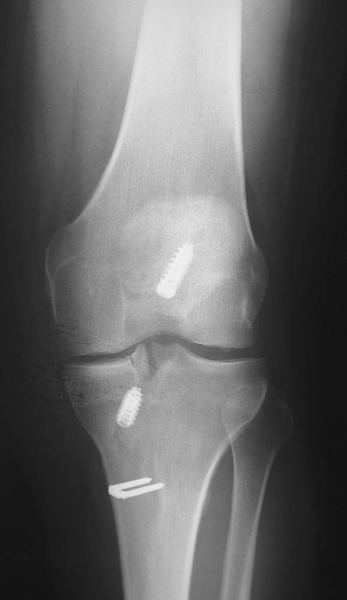

| • | At 7 to 10 days for suture removal and postoperative radiographs ( Fig. 47-16 ) |